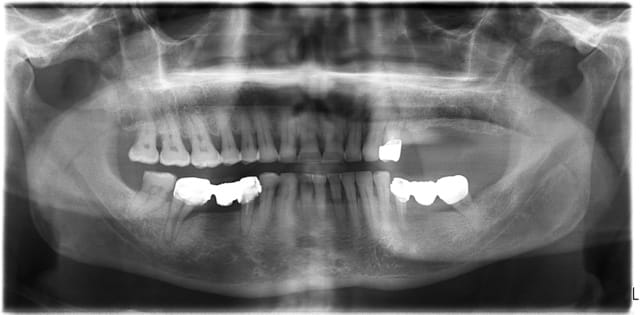

voici mon premier cas d'Extraction implantation Immediate...

Par contre, je pense qu'il faudrait supprimer le nom du patient sur la pano ..

> Par contre, je pense qu'il faudrait supprimer le nom du patient sur la pano ..

oui je m'en suis rendu compte à posteriori...et oui je débute partout....;-)

on ne voit pas trop sur les photos, mais j’espère que tu avais bien assaini en paro auparavant.. parce que la pano n'est pas très belle...

félicitations, et maintenant on attend l'oi =)

oui, la pano date du jour de la consult,

on a fait un assainissement paro et d' autres soins on été entrepris entre temps.

Je dis joli cas, sinon comme les autres, un peu timide sur la longueur, t aurais pu largement lui ramoner le bas fond sinusien pour aller poser un 12 mm sur le distal qui est une 6 mm je présume. Je sais, c est un peu facile après coup. ou sinon radio per op mais difficile à gérer sur le plan de l asepsie.

Non canin c'est un 8mm et 10mm en 24 ET 25

Pour les Summers on va attendre un peu... aller voir un ou deux confères qui en font...